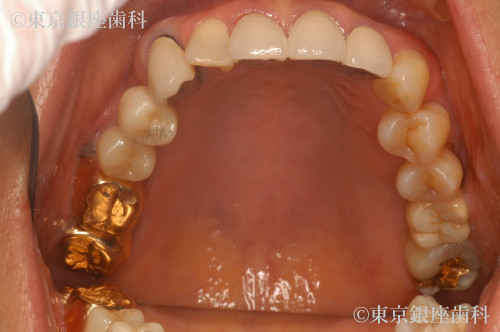

Before

他院で行ったインプラントのリカバリ

上部構造のやり直し

インプラントはしっかりしていたのでうわもののやり直しを実施

セメント固定からスクリュー固定変更したので、今後、緩んでも締めれる